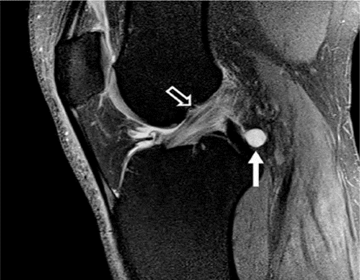

Hình 4. Rách sụn chêm, nang sụn chêm. Hình ảnh coronal xóa mỡ có u nang nhỏ (mũi tên đen) tiếp giáp với thân của sụn chêm bên có vết rách liên quan đến sụn chêm (mũi tên trắng)

Một nang thông số thể hiện sự rò rỉ ngoại vi của dịch khớp qua vết rách sụn chêm, thường nằm ngang theo hướng [8]. Sự hiện diện của u nang tham số có PPV của vết rách là 90%, trừ khi nó nằm liền kề với sừng trước của sụn chêm bên, nơi PPV của vết rách giảm xuống 67% [8].

Đùn sụn chêm lớn hơn 3 mm ra ngoài rìa ngoại vi của mâm chày cũng có liên quan đến rách sụn chêm. 76% vết rách rễ sụn trung gian có đùn và 39% trường hợp đùn có rách rễ trung gian [9].

Một lớp sụn chêm đã được chứng minh là có liên quan đến các vết rách của rễ sụn trung gian sừng sau; một nghiên cứu đã chứng minh rằng các vết nứt sụn xuất hiện ở gốc sau sụn trung gian trong 89% trường hợp, và sụn chêm bị rách trong 98% trường hợp (Hình 4)[9].